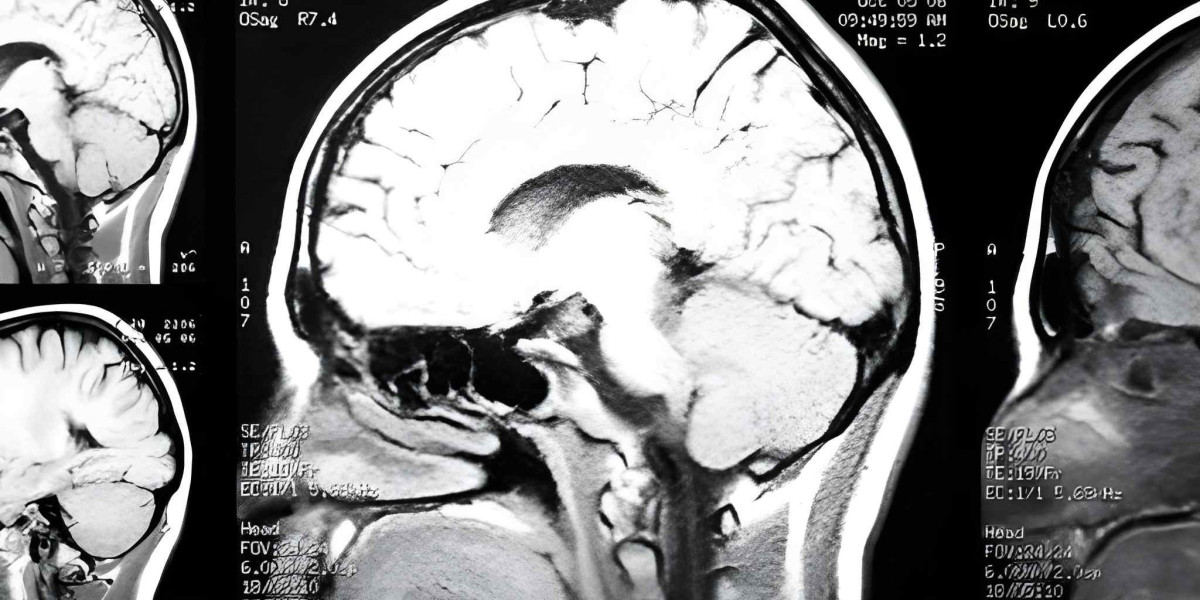

The breakthrough lies in targeting the root cause. Huntington’s Disease is driven by a single, well-defined genetic mutation: an expanded CAG repeat sequence in the huntingtin (HTT) gene. This mutation leads to the production of a toxic protein that damages neurons in the brain. For years, this knowledge was a source of frustration—a clear target without a viable weapon. Gene therapy provides that weapon. Instead of treating the downstream effects, this approach aims to intervene at the genetic level, offering the potential for a lasting, disease-altering impact. This is the scientific foundation that brings the field closer than ever to achieving the first approved disease-modifying therapies for huntington's disease.